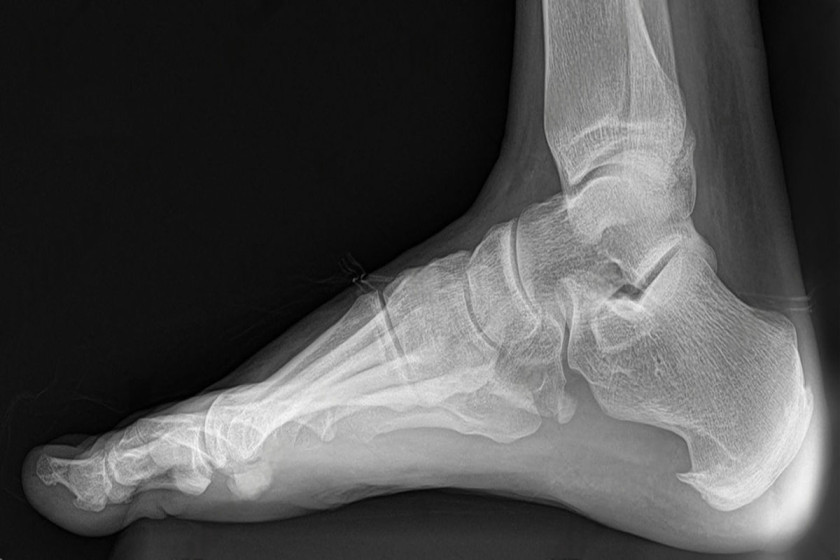

Weight-bearing foot and ankle X-rays for alignment planning in Delhi

• Weight‑bearing X‑rays: AP/lateral/oblique, hindfoot alignment view; hallux angles; Meary’s angle; talar uncoverage.

Hindfoot alignment view and deformity assessment in Delhi